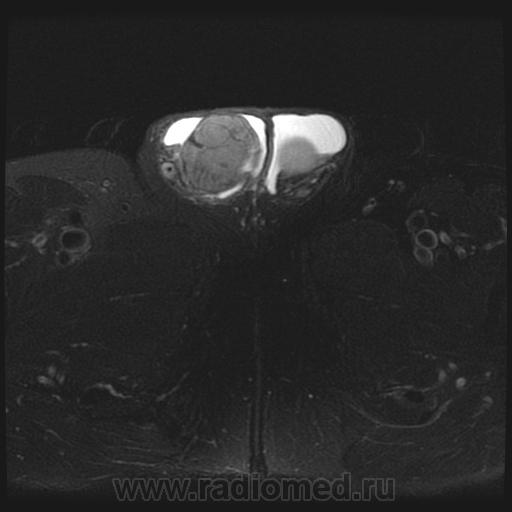

- https://radiomed.ru/sites/default/files/styles/case_slider_image/public/user/1/testis4-t2fs-cor.jpg?itok=awoxfYmC

- https://radiomed.ru/sites/default/files/styles/case_slider_image/public/user/1/testis5-t1-cor.jpg?itok=p35KX7Rk

Считаю, что семинома - не самый вероятный вариант, т.к. структура опухоли достаточно неоднородная, есть распространение на придаток и границы четкие.

"Мужчина, 60 лет. Около 3 месяцев назад появился дискомфорт в области мошонки, увеличение правого яичка."